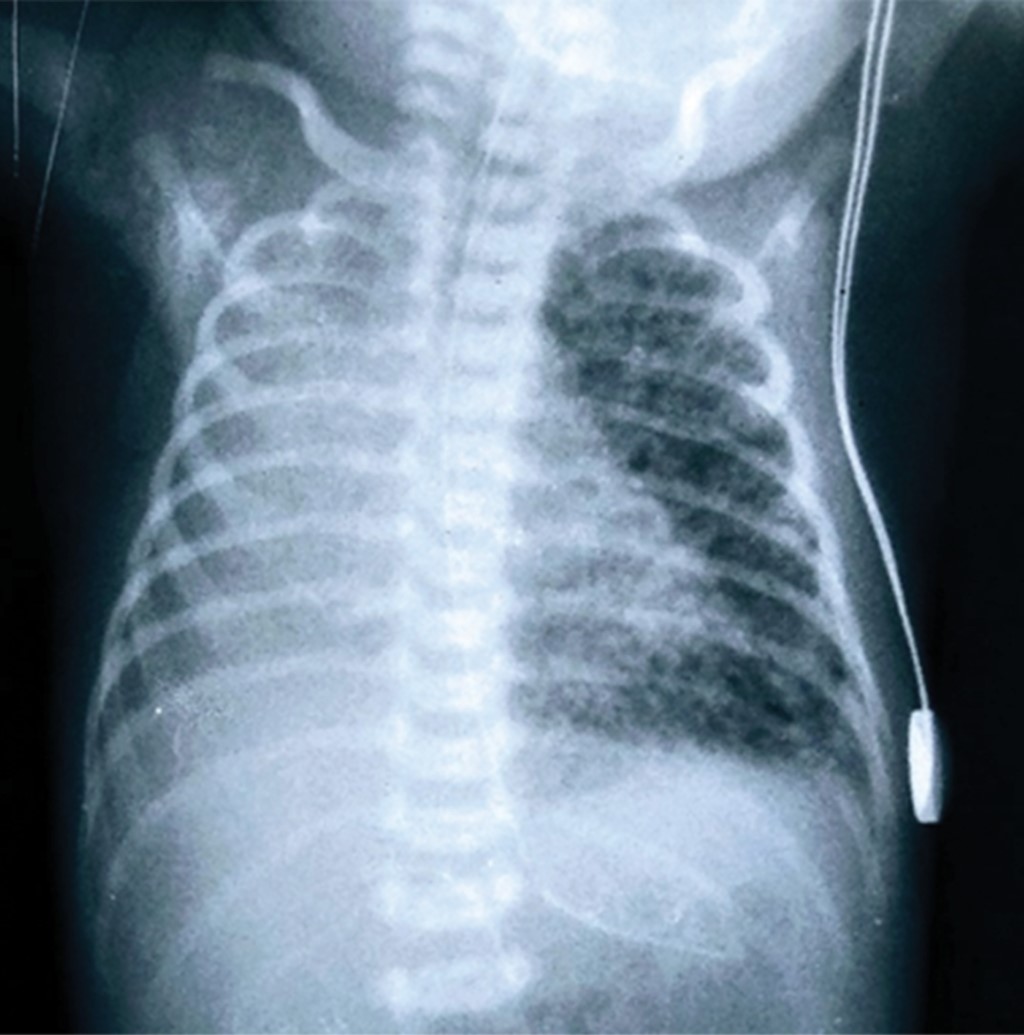

Unilateral interstitial pulmonary emphysema in a newborn

Objective: To describe the clinical outcome of a newborn (NB) with unilateral pulmonary interstitial emphysema (PID) who required selective ventilation of the contralateral lung. Case presentation: This is a 32-week gestation female newborn, who presented respiratory distress syndrome (RDS), requiring mechanical ventilation. On the second day of life, she presented left unilateral interstitial PID. High-frequency oscillatory ventilation was used as treatment for this complication, as well as positioning of the newborn on the affected side, but there was no improvement. Subsequently, after selective ventilation of the contralateral lung was used for 48 hours total resolution of the emphysema was achivied. Conclusion: PID is a serious complication in newborns. The use of selective ventilation to the contralateral lung is a therapeutic alternative for its resolution.

Figure 1